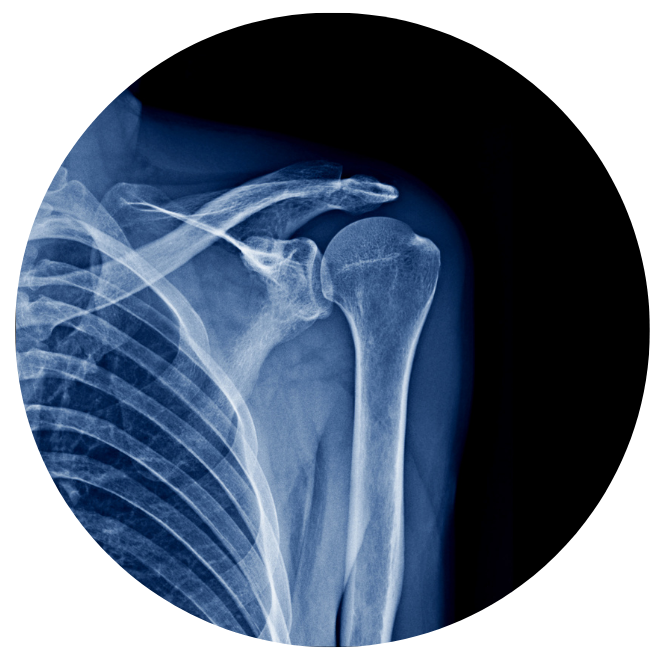

One of the most important decisions is getting the right studies at the right time. A simple X ray can clearly show what is happening inside your joints before the problem gets worse. Choosing to check your pain early is always a Smart Move.